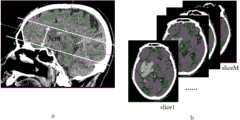

图4空间坐标轴定义。Figure 4 Definition of spatial coordinate axes.

图5Z轴方向候选范围,其中,a为侧裂候选区域矢状位示图;b为侧裂候选区域横断面示图。Fig. 5 Candidate range in the Z-axis direction, in which, a is a sagittal view of the candidate region of the Sylvian fissure; b is a cross-sectional view of the candidate region of the Sylvian fissure.

(1)提取z轴候选范围:提取断层切面面积最大层上下1.5cm,共3cm范围为侧裂所在z轴方向候选层(slice1、……sliceM),示意图如图4和5。(1) Extract candidate z-axis ranges: extract 1.5 cm above and below the layer with the largest section area of the fault, and a total range of 3 cm is the candidate layers in the z-axis direction (slice1, ... sliceM) where the Sylvian fissure is located. The schematic diagrams are shown in Figures 4 and 5.

(2)提取y轴方向候选范围:遍历(slice1、……sliceM),计算各断层slice头骨上缘与下缘之间的距离H,H均分为4份,第2/4区域为侧裂所在区域(slice1y、……sliceMy),示意图如图6。(2) Extract the candidate range in the y-axis direction: traverse (slice1,...sliceM), calculate the distance H between the upper edge and lower edge of the skull of each fault slice, H is divided into 4 parts, and the 2/4 area is the lateral fissure The area (slice1y , ... sliceMy ) is shown in Figure 6.